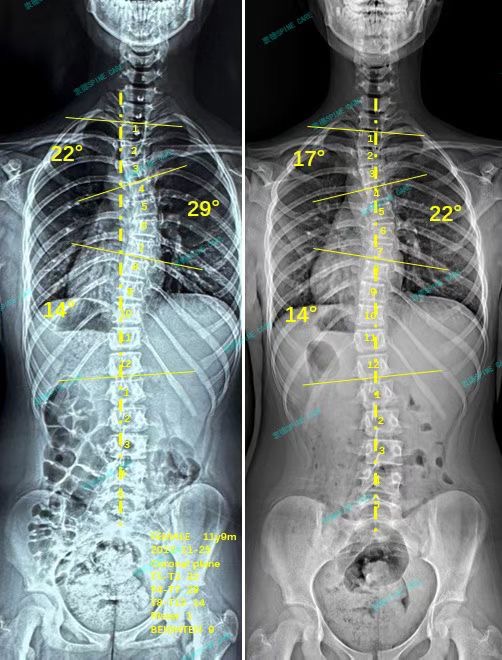

我是小强,三个月纯训练,胸弯降低7度、上胸弯降低5度,继续坚持!

案例主人:小强 发现侧弯年龄:12岁 侧弯情况:Cobb角度29度

3个月后又到了拍x片的时候,我非常紧张,但是结果让人轻松!我的胸弯从29度降到了22度,上胸弯从22度降到17度,胸椎旋转也从5度降低到了3度,我的体态看起来比之前挺拔了不少,爸爸妈妈和我都很开心!我们决定继续在衷德坚持锻炼!

Three months later, it was time to take x-ray again. I was very nervous, but the results relaxed me! My chest curve has dropped from 29 degrees to 22 degrees, my upper chest curve has dropped from 22 degrees to 17 degrees, and my thoracic rotation has also dropped from 5 degrees to 3 degrees. My posture looks much taller and more straight than before. My parents and I are very happy! We decided to continue to exercise in Zhongde!